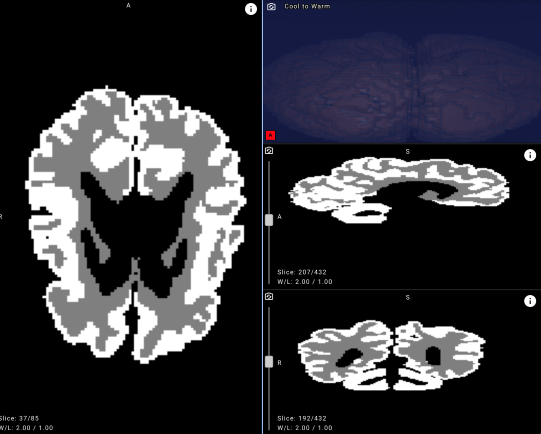

Erken tanı, hastalığın seyri ve etkili bir rehabilitasyon için büyük önem taşıyor. Ancak serebral palsiyi yaşamın ilk 12 ayında saptamak, modern tıbbın en zor alanlarından biri olarak kabul ediliyor. Bebek beyninin olağanüstü hızlı gelişimi ve beyin MR’ında gri ve beyaz madde arasındaki kontrastın düşük olması, yani beynin korteksini oluşturan ve üst düzey işlevleri sağlayan dokuların birbirinden zor ayırt edilmesi, tanı sürecini oldukça güçleştiriyor.

Yarışma, dünyanın dört bir yanından geliştiricileri bir araya getirdi ancak önemli bir sorunu da ortaya çıkardı: Açıklanabilir veri eksikliği. Özellikle, klinik kullanım amacıyla yapay zekâ modellerini eğitmek için gerekli olan gri ve beyaz maddenin ana hatlarını gösteren segmentasyon maskeleri çok azdı. iSeg-2019 veri seti sadece 15 açıklamalı görüntü içerirken, üniversitenin arşivinde 1500 hastanın açıklaması olmayan MRI taramaları bulunuyordu.

Bu eksikliği gidermek amacıyla Yandex araştırmacıları, tıp uzmanlarıyla birlikte yeni açıklamalar oluşturdu, özel bir sinir ağı mimarisi geliştirdi ve kapsamlı makine öğrenimi deneyleri yürüttü. Sonuçta ortaya çıkan model, yapılan iç değerlendirmelerde bebek beyinlerinde gri ve beyaz maddeyi ayırt etmede yüzde 90’ın üzerinde bir doğruluk oranına ulaştı ve klinik uygulamalar için güçlü bir potansiyel sergiledi.

- Doğruluk ve objektiflik artıyor. Yüzde 90’ın üzerinde doğruluk oranına sahip model, bebek beynindeki gri ve beyaz maddeyi net biçimde ayırıyor ve oranlar ölçüyor.